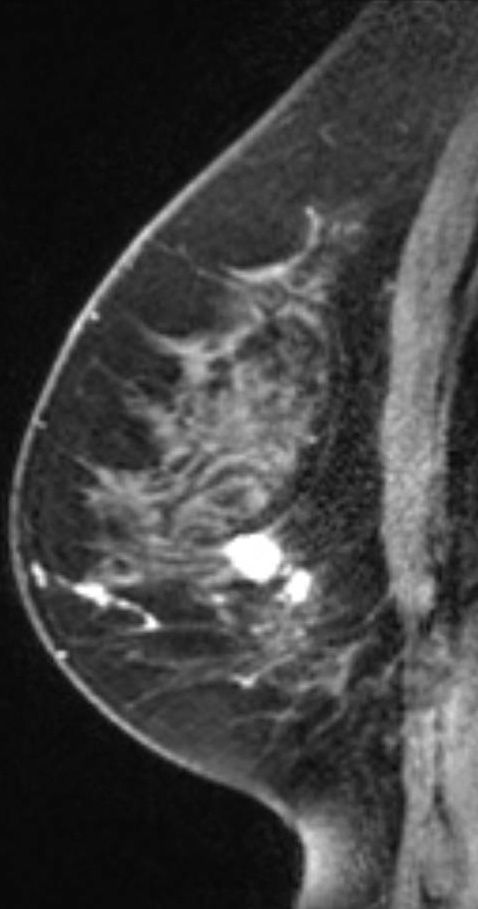

Case History: 67-year-old female with progressive increase in size of left breast for five years.